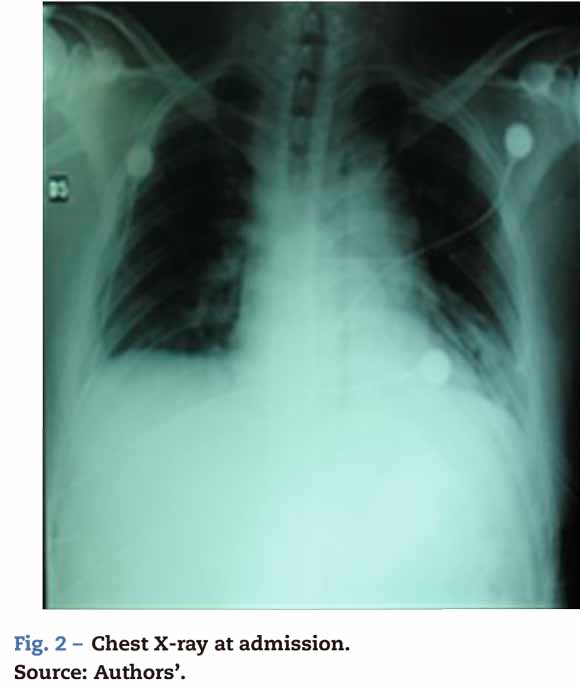

The Ethics Committee of our organization authorized this case discussion of a 30-year old male patient who was the driver in a car crash but did not loose consciousness. The physical examination revealed chest trauma with dissection of the descending aorta, left femur fracture, fracture of the left distal radius and of the fifth left hand digit, in addition to pneumothorax and pulmonary contusion of the left lung. The patient was managed with closed thoracotomy (see Fig. 2).